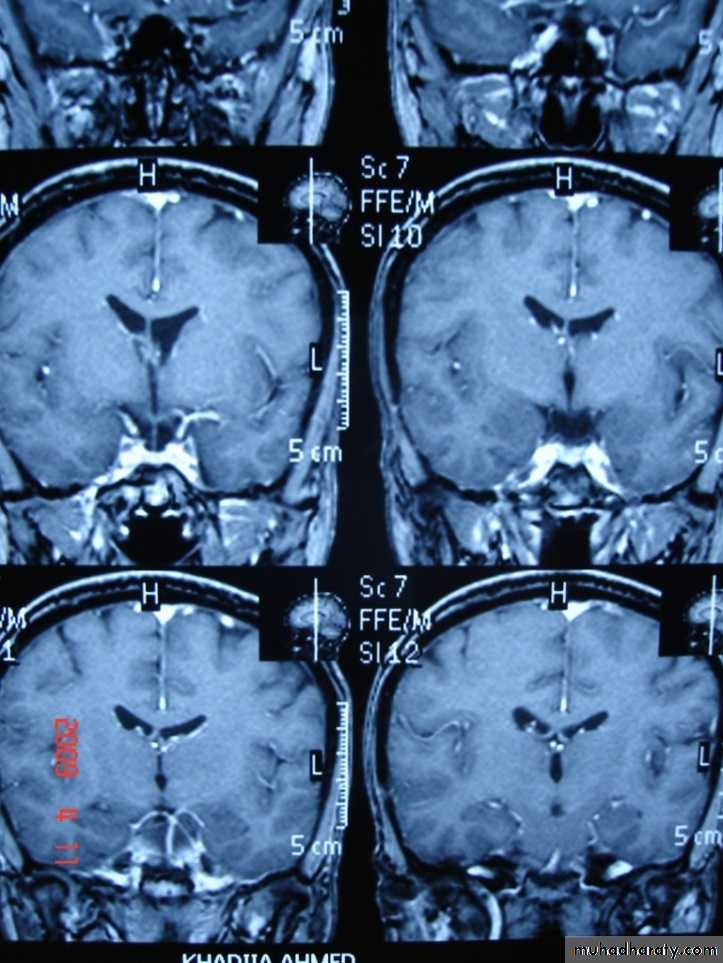

MULTIPLE SCLEROSIS:

-common neurological disorder.

-characterized by disseminated plaques of demyelination & gliosis throughout the neuraxis.

-the sites of election are:

1.periventricular.

2.optic pathways.

3.brainstem.

4.cerebellar white matter & peduncles.

5.spinal cord.

-young adults are primarily affected.

-MRI is more sensitive than CT in the demonstration of MS plaques.

- the most characteristic appearance is that of peri ventricular nodular Hyper intense lesions on T2 weighted images.

-the plaques are also well seen at the gray- white matter interfaces.

-MRI can even image lesions in the spinal cord , brainstem & cerebellum.

-multiple cerebral lesions are seen in over half the patient presenting with a single episode of optic neuritis.

-some lesion may show a central area of greater signal intensity , resembling a target.

-contrast enhancement after giving gadolinium occurs in the acute phase indicating activity & in the chronic phase doesn't enhance.

SAGITAL FLUID ATTENUATION INVERSION RECOVERY SEQUENCE: OVOID PLAQUES ( HIGH SIGNAL INTENSITY) , WHICH ARE PERPENDICULAR TO LATERAL VENTRICLE.